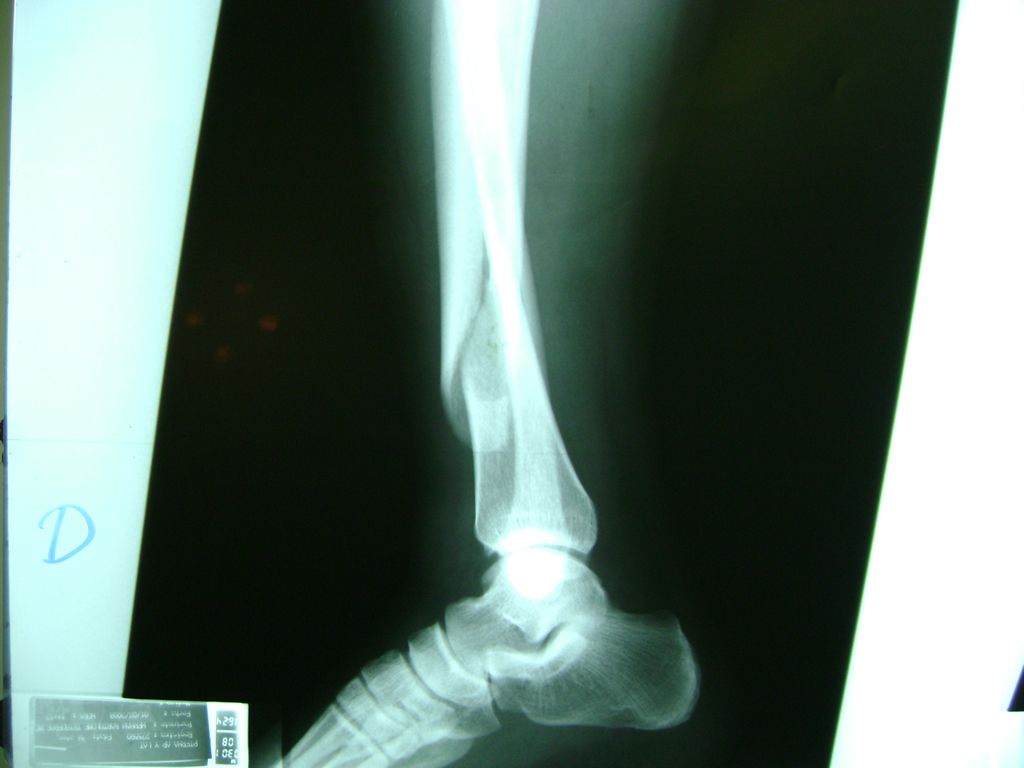

Cirugías de Peroné y Tibia

La mayor parte de las roturas implican a la parte proximal del hueso (parte del hueso próximo a la rodilla) o a la parte distal (parte del hueso cerca del tobillo).

Debido a la fina cobertura de piel que recubre la tibia y el peroné, las fracturas generalmente son abiertas, es decir, el hueso roto rasga la piel, atravesándola. Las fracturas de tibia y peroné generalmente se producen por un fuerte impacto o torsión.